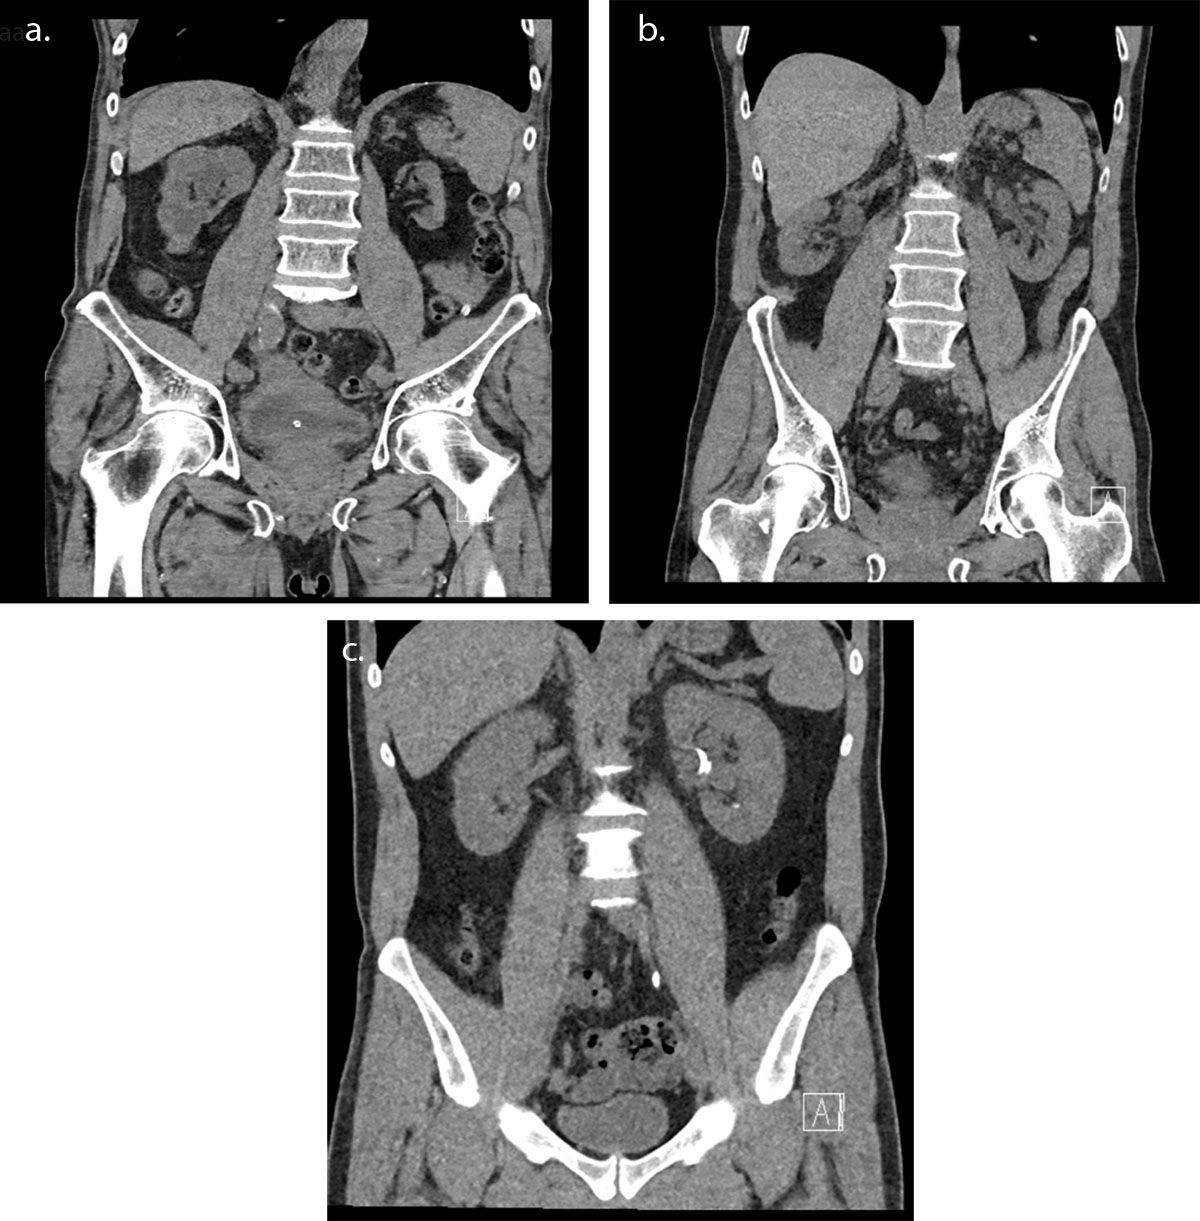

Figure 1 illustrates 3 examples of CT-scans in the coronal plane from patients with similar diameters and different acquisition lengths and/or protocol selections.

CT examination for urolithiasis in coronal section for three patients of similar diameters: (a) wrong acquisition length and protocol selection – DLP 206.1 mGy.cm (b) right protocol but wrong acquisition length – DLP 82.4 mGy.cm (c) right protocol selection using Tin Filter and right acquisition length – DLP 34.3 mGy.cm.

As illustrated in Figure 1, the dose reduction can be very important, as high as 83%, which should largely motivate stakeholders to use low-dose protocols.